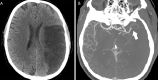

In this article we will review the imaging features of coronavirus disease 2019 (COVID-19) across multiple modalities, including radiography, CT, MRI, PET/CT, and US. Given that COVID-19 primarily affects the lung parenchyma by causing pneumonia, our directive is to focus on thoracic findings associated with COVID-19. We aim to enhance radiologists' understanding of this disease to help guide diagnosis and management. Supplemental material is available for this article. © RSNA, 2020.